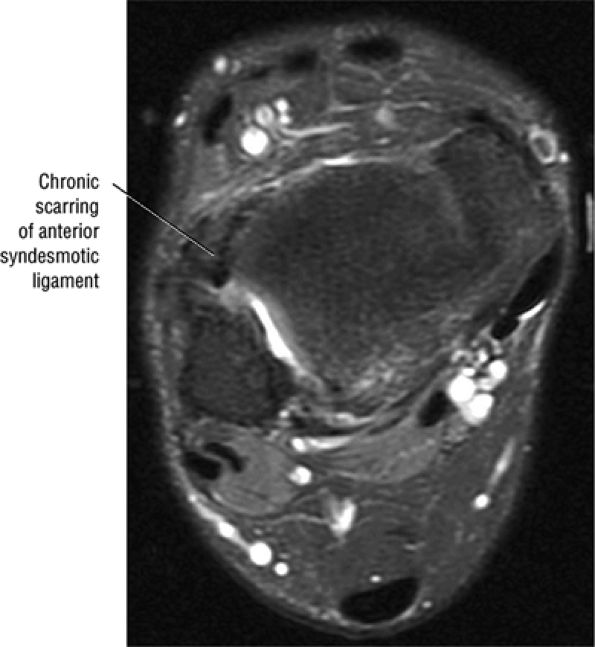

FIGURE 5.27 ● Axial anatomy of the ankle and foot. (A) The flexor digitorum longus, flexor hallucis longus, peroneus brevis, soleus, and extensor digitorum muscles are examined at this level for strain, tears, or fatty atrophy that may suggest denervation. (B) The tibialis anterior, extensor hallucis longus, and extensor digitorum longus tendons are examined on every ankle MR examination. Extensor tendon pathology is frequently overlooked if these tendons are not included as part of the ankle checklist. (C) Tears and sprains of the anterior syndesmotic ligament are a frequent cause of persistent ankle pain following ankle sprain. The syndesmotic ligaments are thick, tough ligaments that are important ankle stabilizers, and delayed diagnosis of syndesmotic tears may result in significant degenerative arthrosis at the tibiotalar joint due to the resulting ankle instability. The syndesmotic ligaments course obliquely inferiorly from the tibia to the fibula and are not usually visualized in their entirety on a single axial image; rather, their course is followed on at least two or three successive axial images. (D) The peripheral margin of the peroneal tendons and tibialis posterior tendon should normally never extend beyond the peripheral margins of the lateral and medial malleoli, respectively. Tendon subluxation around the posterior corner of either malleolus is indicative of a tear of the overlying flexor retinaculum (medially) or peroneal retinaculum (laterally). When the retinacula are torn, the tendon is free to intermittently sublux or dislocate, leading to tendon degeneration, pain, and tendon dysfunction. (E) Suspected osteochondral lesions of the talar dome are visualized and further characterized on axial images through the top of the talar dome. (F) The peroneus brevis tendon may normally appear somewhat flattened. However, as the tendon degenerates, it becomes U-shaped and drapes around the anterior aspect of the peroneus longus and becomes impinged between the peroneus longus tendon and the lateral malleolus. With further degeneration, the peroneus brevis may split or completely rupture. (G) Evidence of anterior talofibular ligament injury is visualized on the majority of MR ankle examinations and appears as thickening, intermediate signal with ill-defined fibers, or attenuation of the ligament. This is commonly asymptomatic. (H) Because the flexor hallucis longus tendon sheath communicates with the tibiotalar joint, fluid may normally be present within the tendon sheath in proportion to the amount of fluid in the tibiotalar joint. If there is fluid within the tendon sheath out of proportion to that seen in the tibiotalar joint, tenosynovitis is most likely present. The finding of flexor hallucis longus tenosynovitis should prompt a search for an os trigonum, as impingement of the flexor hallucis longus tendon between an os trigonum and the posterior tibial plafond is a common cause for FHL tenosynovitis. (I) The calcaneofibular ligament (CFL) passes anterior and medial to the peroneal tendons. On the image at which the CFL passes directly medial to the peroneus brevis tendon, the appearance of the peroneus brevis and the CFL side by side is occasionally mistaken for a split peroneus brevis tendon. (J) Dilated posterior tibial veins within the tarsal tunnel occasionally compresses the tibial nerve. In the setting of clinical suspicion for tarsal tunnel syndrome or if there is evidence of muscle denervation on MR images, the size of the posterior tibial veins should be described. (K) The spring ligament is identified at this axial image location, extending from the anteromedial calcaneus to the posteromedial navicular. Tears of the spring ligament may result in medial instability and hindfoot valgus. (L) The posterior tibialis tendon (PTT) may normally become thickened and fan-like as it passes posterior to its navicular insertion (prior to also inserting on the cuneiforms and the base of the second through fourth metatarsals). In the absence of other findings, the thickening of the PTT at this level should not be mistaken for focal tendinosis. (M) On inferior images through the ankle, Lisfranc's ligament is occasionally included in the FOV. Lisfranc's ligament extends from the medial cuneiform to the base of the second metatarsal. If Lisfranc's ligament is included in the FOV, the status of the ligament should be described, as undiagnosed Lisfranc ligament tears can lead to debilitating midfoot arthrosis. (N) As the medial and lateral tendons turn from their vertical course to a horizontal course along the plantar aspect of the foot, the tendons may demonstrate a magic-angle artifact, causing the tendons to appear gray on short-TE images, mimicking tendinosis. Correlation with images using longer TE values is advised in such situations.

FIGURE 5.43 High Ankle Ligaments.